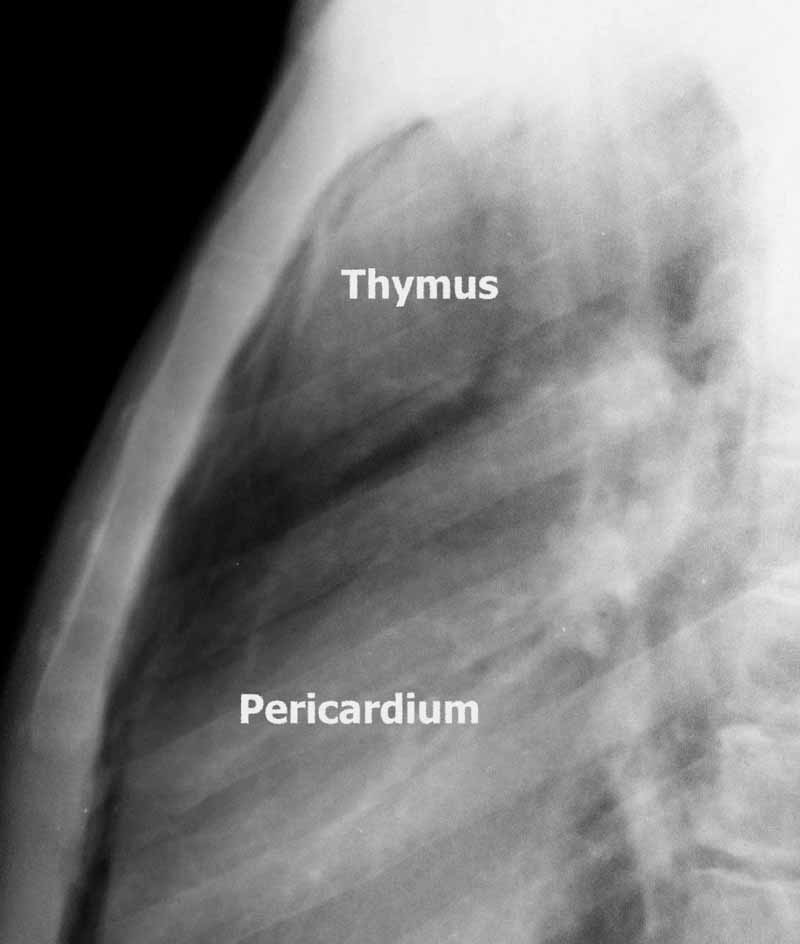

Фотографии вилочковой железы тимуса: структура и функции